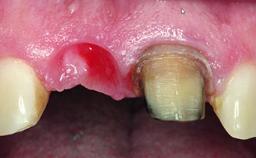

Replacement of an Ankylosed Upper Left Central Incisor: Bone Augmentation and Socket Grafting, Late Placement of an RC Bone Level Implant

Soft Tissue Contour and Volume Significantly deficient